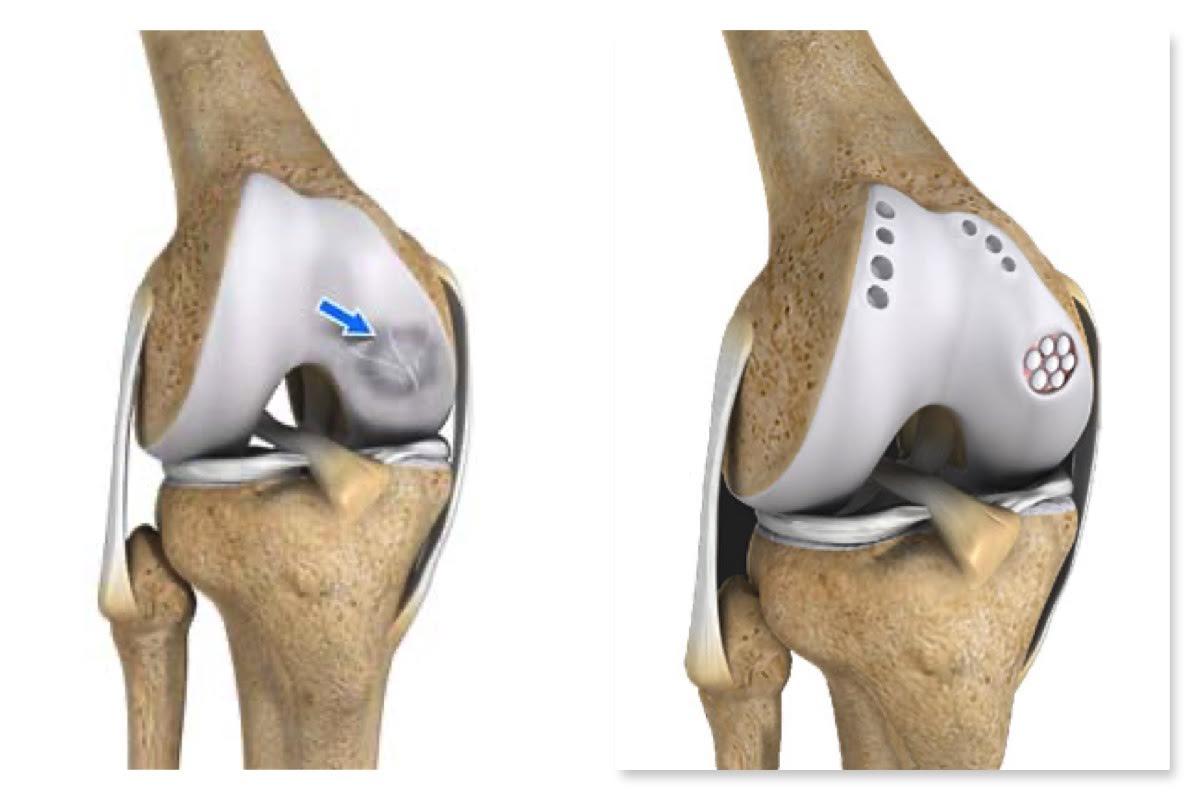

Joint preservation procedures are advanced medical and surgical techniques aimed at maintaining the natural joint structure, function, and mobility, thereby delaying or avoiding the need for joint replacement. These procedures are particularly beneficial for younger, active individuals suffering from early to moderate joint damage due to conditions like osteoarthritis, cartilage injuries, or ligament tears. Common joint preservation strategies include arthroscopic surgery, cartilage restoration, osteotomies (bone realignment), and biologic treatments such as platelet-rich plasma (PRP) or stem cell therapy. The primary goal is to relieve pain, improve joint function, and enhance the quality of life by preserving the patient’s own joint tissues whenever possible.